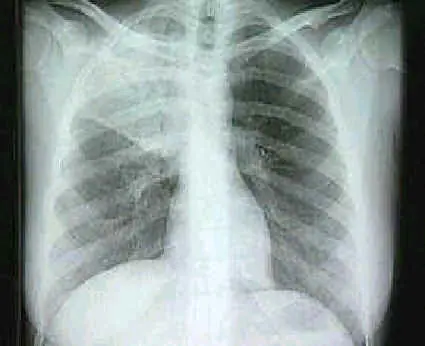

Un fumador de paquete y medio de cigarrillos por día recibe en los bronquios 400 rads de radiaciones alfa por año, lo que equivale a 300 radiografías de tórax, es decir, casi una por día.

Comparación entre un pulmón sano y uno de un fumador